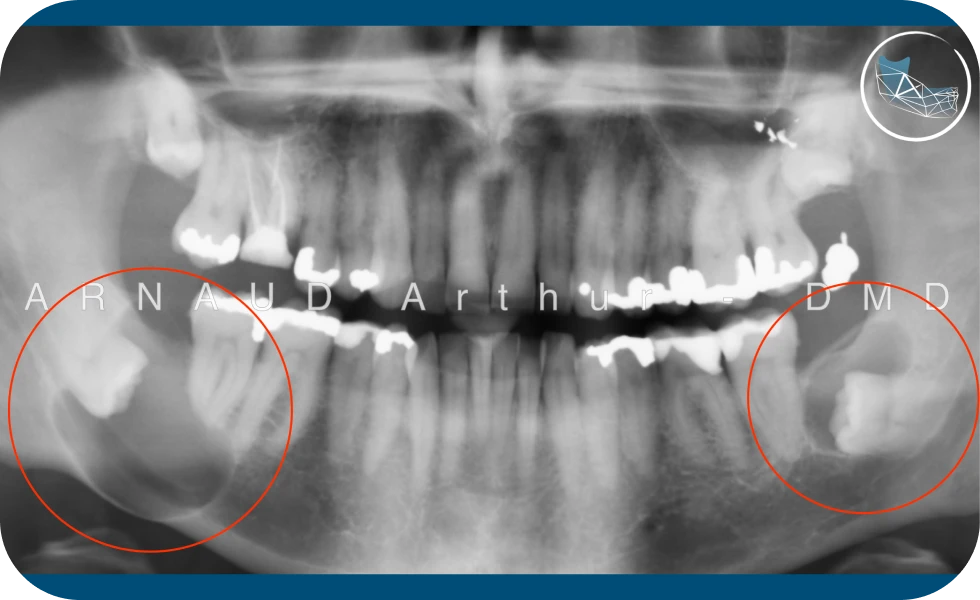

Cas de lésions double sur les dents de sagesses inférieures chez un patient adulte (dont la mâchoire à gauche sur la radiographie est fragilisée par la destruction osseuse)